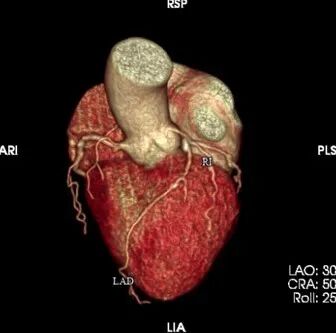

心脑联合造影

-- 右侧颈内起始部中度狭窄,经前交通向左侧代偿

波科支架怎么样​径技·第165期|7F经桡入路下的颈动脉狭窄支架成形术一例_https://www.jmylbn.com_新闻资讯_第11张

波科支架怎么样​径技·第165期|7F经桡入路下的颈动脉狭窄支架成形术一例_https://www.jmylbn.com_新闻资讯_第12张

波科支架怎么样​径技·第165期|7F经桡入路下的颈动脉狭窄支架成形术一例_https://www.jmylbn.com_新闻资讯_第13张

-- 左侧颈内起始部重度狭窄